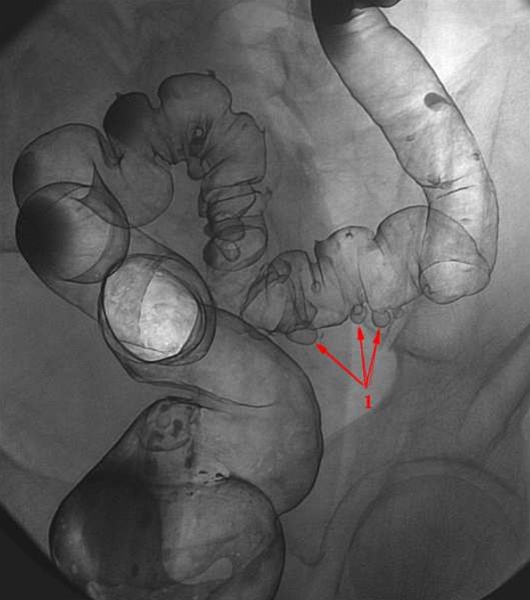

Dobbeltkontrast-røntgenbillede af endetarm (rektum) og tyktarmens nederste stykke (sigmoideum) med flere divertikler i varierende størrelser (røde pile ved 1). I dag anvender man næsten altid CT scanning i stedet for røntgen til at undersøge for divertikler.